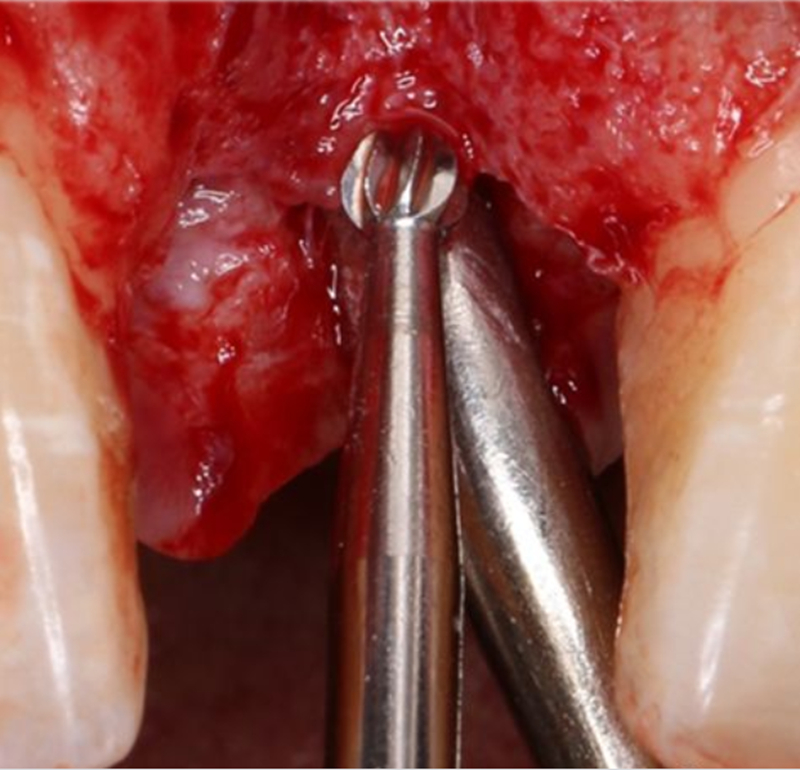

定點

1.4mm小球鉆定點 △

2.3mm中號球鉆打開皮質(zhì)骨△

在易植美實時導(dǎo)航系統(tǒng)中,計算機引導(dǎo)球鉆精準按照術(shù)前設(shè)計定位△